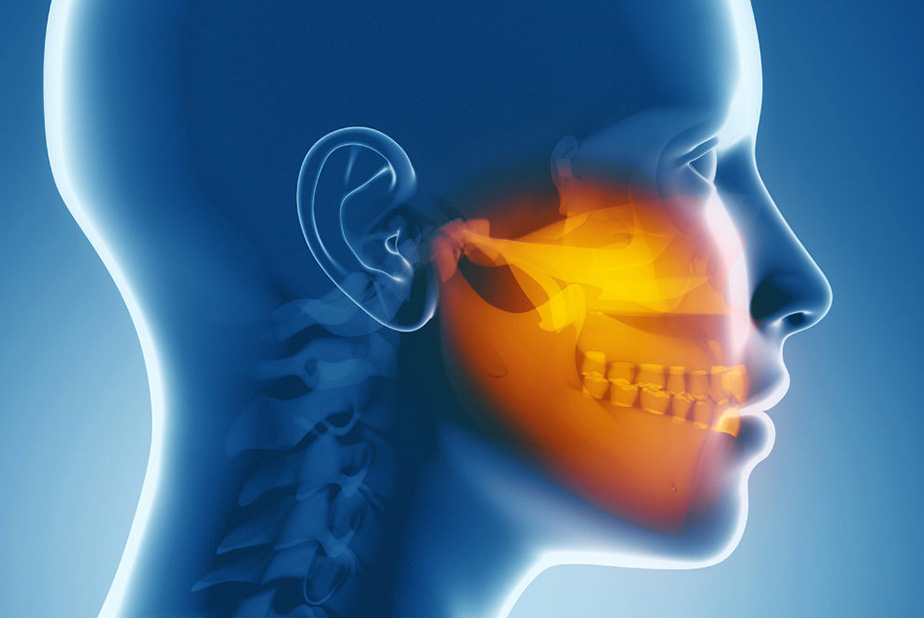

In questo contesto, uno studio condotto da ricercatori della Nuh Naci Yazgan University di Kayseri, in Turchia, ha esplorato nuove prospettive sul legame tra le caratteristiche cervicali e le patologie temporomandibolari. L'obiettivo principale dello studio era chiarire la complessa associazione tra le strutture cervicali e i TMD.

Durante la ricerca, gli autori hanno esaminato le relazioni di rotazione tra diverse strutture: il cranio e l'atlante (la prima vertebra cervicale), l'atlante e l'assile (la seconda vertebra cervicale) e tra la mandibola e l'atlante. Successivamente, hanno valutato la correlazione tra queste rotazioni e i disordini temporomandibolari.

Il recente studio ha portato a una maggiore comprensione dell'impatto della postura cranio-cervicale nei pazienti con disordini temporomandibolari (TMD). I risultati hanno evidenziato che la postura cranio-cervicale in questi pazienti è più significativamente influenzata rispetto a coloro che non soffrono di TMD.

Una delle principali conclusioni dello studio è l'importanza di esaminare il sistema scheletrico in un contesto tridimensionale. Ciò significa prendere in considerazione diverse immagini trasversali per analizzare in modo approfondito l'allineamento e la relazione tra la mandibola e le vertebre nel piano trasversale. Questo approccio consente una comprensione più dettagliata e accurata delle complesse dinamiche tra le strutture cranio-cervicali e i TMD.

In sintesi, lo studio sottolinea l'essenzialità di un'analisi approfondita dell'interconnessione tra la postura cranio-cervicale e i TMD. Questa prospettiva può offrire nuove intuizioni nella diagnosi e nel trattamento dei TMD, evidenziando l'importanza di un approccio olistico che consideri non solo l'articolazione temporomandibolare ma anche le sue relazioni con le strutture circostanti.